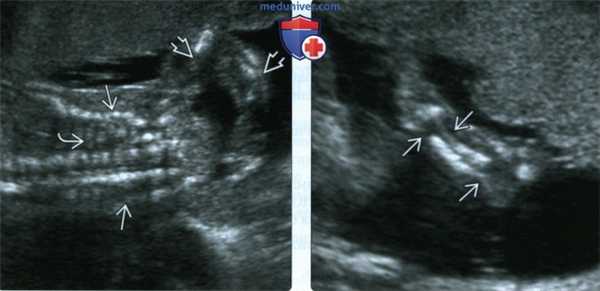

(Слева) УЗИ грудной клетки и верхней конечности плода во II триместре, фронтальная плоскость. Грудная клетка уменьшена, ребра неправильной формы с множеством переломов. Многочисленные переломы костей руки.

(Справа) Тот же случай, визуализация предплечья. Неоднородная оссификация локтевой и лучевой костей. Костные сегменты нередко смещены, за счет чего кость выглядит изогнутой или искривленной. В данном случае диагностирован перинатальнолетальный НО (II тип).

2. УЗИ при несовершенном остеогенезе у плода:

• Конечности:

о Укорочение и искривление трубчатых костей вследствие переломов

о Формирование ложных суставов

о Формирование мозолей придает костям «скомканный» вид

о Минерализация снижена

• Грудная клетка:

о При перинатально-летальном типе - множественные переломы ребер (в виде «рахитических четок»)

о Визуализируется «излишне отчетливо», реверберационный артефакт отсутствует:

- Слабая минерализация черепа

о Череп деформируется при обычном нажатии датчиком